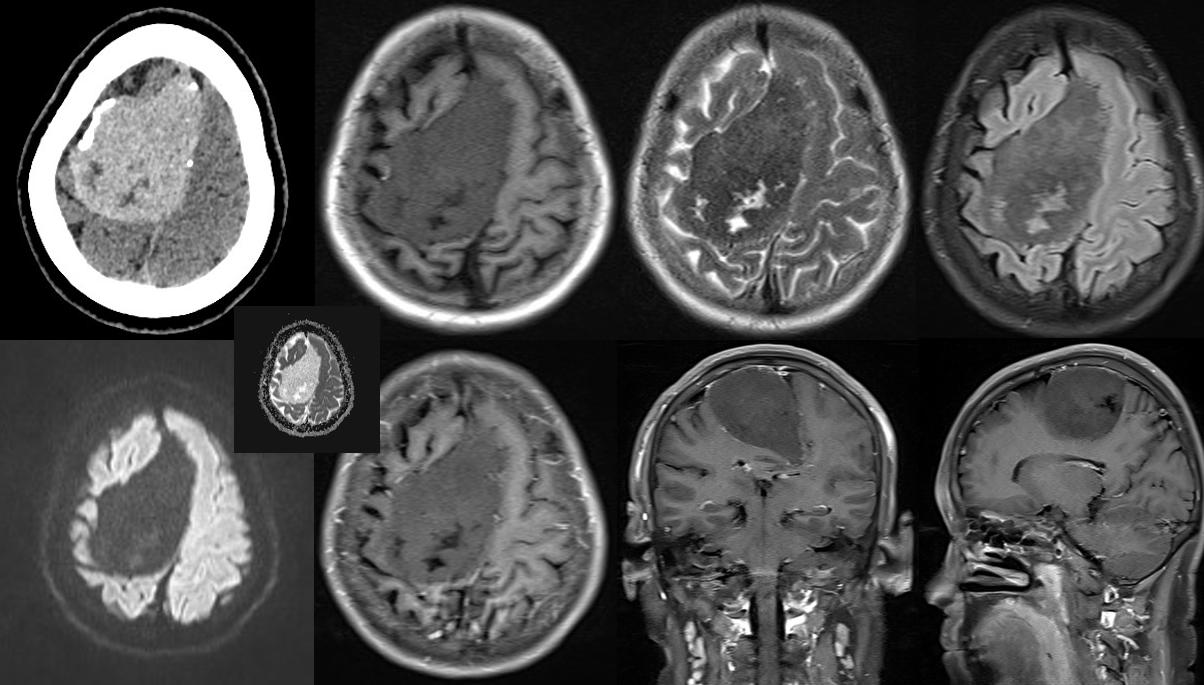

病例一

病史:59Y;女;主诉:头晕、头痛伴恶心3年,检查发现颅内占位10天

CT:右额部大脑镰旁见不均匀高密度灶,较大截面约7.3X5.6cm,内见不规则低密度区,边界清边缘见点片状钙化,病变宽基底附着于颅骨内面及大脑镰,并沿大脑镰下缘向对侧延伸,左侧侧脑室受压,邻近脑组织受压推移,脑实质内未见明显异常密度灶。

MRI:右额部大脑镰旁见长短T1等长T2 异常混杂信号灶,FLAIR呈等低信号,其内见斑片状高信号DWI 未见扩散受限,大小约 7.9X5.0X3.8cm,边界清,周围脑实质及左侧侧脑室明显受压推移,中线结构向左侧移位,增强扫描病灶未见明显强化。双侧半卵圆中心另见多发斑点、片状等长T1长T2信号灶,FLAIR 呈高信号,DWI 未见弥散受限,增强扫描未见异常强化灶。

CT:右额部大脑镰旁占位性病变,符合脑膜瘤 CT表现,必要时 MI检查;

MRI:右额部大脑镰旁占位性病变,考虑非典型脑膜瘤MRI表现脑多发缺血灶。建议结合临床。

病理:软骨瘤